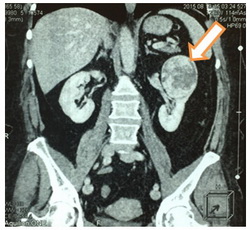

При МРТ органов брюшной полости и забрюшинного пространства: в верхнем и среднем сегментах определяется объемное образование неправильной формы неоднородной структуры размерами 6,8х6,2х5,7см., активно накапливающее контрастный препарат.

При МСКТ: в верхнем и среднем сегментах левой почки по передне-латеральной поверхности определяется мягкотканное образование неправильной формы неоднородной структуры размерами 6,9х5,8х6,8см.